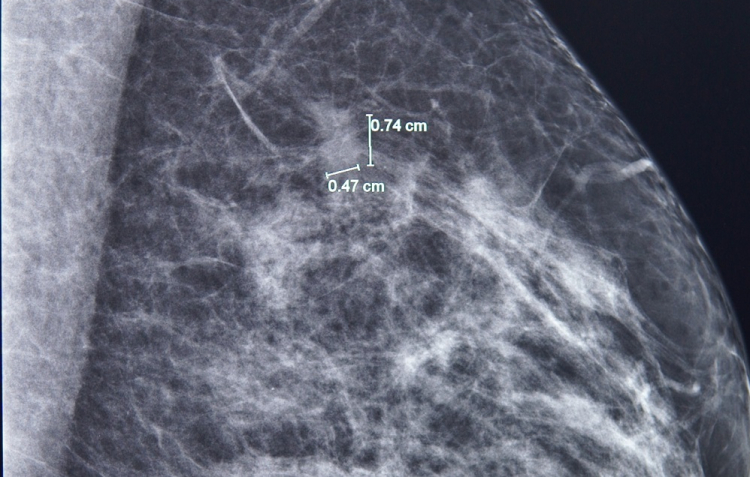

Kết quả nhũ ảnh tìm ra một tổn thương nhỏ, khoảng 7mm ở vú trái. BS.CKI Phùng Ngọc Thư - Trưởng Trung tâm Chăm sóc tuyến vú FV cho bệnh nhân chụp thêm cộng hưởng từ (MRI) do mô vú của bà A. khá đặc. Qua phim chụp MRI, bác sĩ Thư phát hiện thêm một nốt tổn thương khác, chỉ 3mm.

Phát hiện tổn thương 7mm ở vú trái bằng chụp nhũ ảnh - Ảnh: FV